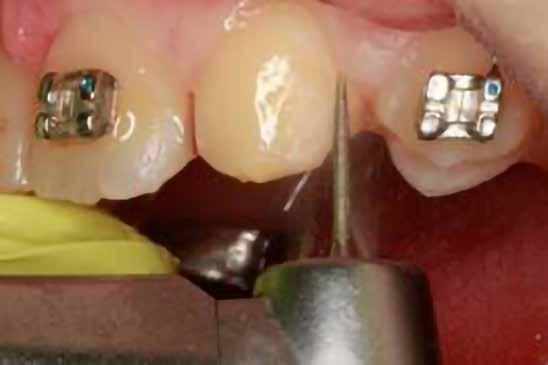

Szemfog becsiszolás

A szemfog elcsiszolásához piros gyémántfúró javasolt, finom szemcsézettséggel, 27-76 µm (okkluzálisan lekerekített – Rodentica, speciális hegyű 806314466514031, Komet 8833), gyorsítóval (max 160 000 fordulat/perc) megfelelő hűtés mellett, legalább 50 ml/perc. Ezt követi a felület kidolgozása és polírozása sárga gyémántcsiszolóval, extra finom szemcsézettséggel, 10-36 µm (Rodentica 806314466504031) és narancssárga Sof-Lex korongokkal (finom alumínium-oxid szemcsék 3-40 µm, extra finom, narancssárga-sárga, alumínium-oxid kristályok mérete 1,7 µm) könyökdarabban (25000 fordulat/perc) megfelelő hűtés mellett min. 50 ml/perc (2. a-d. ábra).

A szemfog megfelelő inklinációjának eléréséhez az oldalsó metsző helyén a palatinális felszínt is el kell csiszolni. Ennek a felületnek nem szabad interferenciát okoznia a harapásban, és lehetővé kell tennie a megfelelő metszőfog-vezetést [14]. A formázás előtt meg kell vizsgálni a szemfog vesztibulo-orális pozícióját. Lapos vesztibuláris felszínnel rendelkező szemfog esetén szükség lehet egy elsőrendű hajlításra a középső metsző és szemfog között (főleg, ha a szemfogon egy oldalsó metsző bracket van, melyben a beépített in-out érték magasabb) annak érdekében, hogy elérjük a megfelelő vesztibulo-orális pozíciót a fognyak szintjén, és elkerüljük a palatinális elcsiszolást (3. a-b ábra), [39].

Abban az esetben, ha a szemfognak kifejezettebb a központi lóbusa, a palatinális felszínről is el kell csiszolni, nem csak a vesztibuláris felszínről [40, 41]. A vesztibuláris felszín kifejezett elcsiszolása esetén ez már a dentint is érintheti, ami megnehezíti az esztétikai helyreállítást (a sárga dentin átüthet és a ragasztás is nehezebb ehhez a felülethez). Ezért a vesztibulárisan domború szemfogakat javasolt palatinálisabban pozicionálni, ami – együtt

38 e-Journal ORTHODONTIA

2. a–d ábrák

a nagyobb mértékű palatinális elcsiszolással – lehetővé teszi a felépítmény kiterjesztését a vesztibuláris felszínen és a központi lóbus álcázását [39].

A zománc elcsiszolásának mértékét az orális és incizális felszínen a harapás határozza meg, ennek vizsgálatához tükröt és artikulációs papírt használunk [36]. Ideálisan, teljes interkuszpidációban a frontális kontakt olyan enyhe, hogy az artikulációs papír kicsúszik, míg propulzióban, metsző fogvezetésnél a jelölésnek a palatinális felszín incizális harmadában kell lennie mind a középső metszőn, mind a szemfogon. A gyémánteszközök legalkalmasabb formája a palatinális elcsiszoláshoz a lándzsa és rögbi alakú (Komet 0640, piros finom lándzsa Rodentica 806314257514020 (max. 300 000 fordulat/perc), rögbi Rodentica 800314278514020 finom piros (27-76 µm) gyorsítóban. Ezt követően könyökdarabba fogott Sof-Lex korongokkal szükséges polírozni (4. a-b. ábra).

3. a–b ábra: .019x.025” acél mint befejező fogszabályozóív vesztibuláris hajlításokkal a 11-13., a 21-23., valamint a 24-25. és a 14-15. fogak között. 4. a-b. ábra: A szemfog palatinális felületének formázása (a, Rodentica 257) és polírozása narancssárga Sof-Lex koronggal (b). A braketeket már eltávolították ezekről a fogakról.